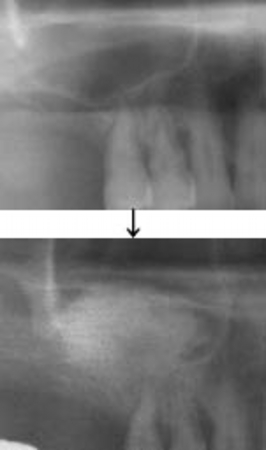

ソケットリフト症例(治療前後のCTもしくはパノラマ写真)

↓

↓